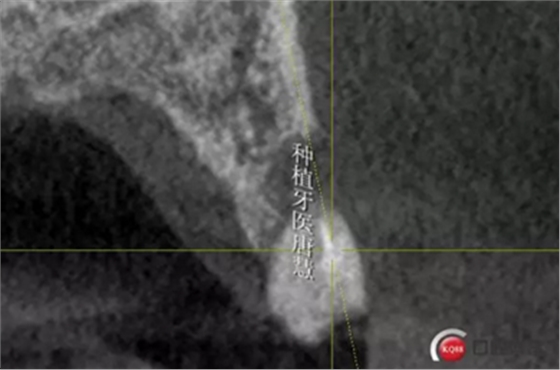

頰側(cè)骨皮質(zhì)缺失

16牙槽骨條件尚好